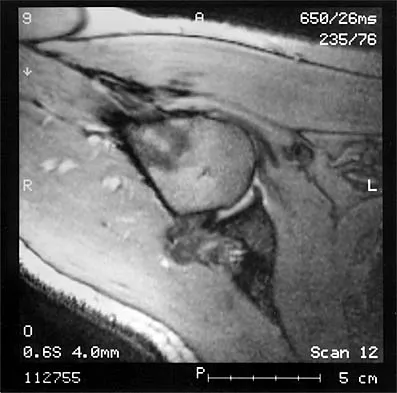

The MRI scan of the shoulder shown in Figure 2 was performed with the arm in abduction and external rotation. The image reveals what condition?

Explanation

Internal impingement of the shoulder is now a well-recognized cause of shoulder pain in the throwing athlete. First described by Walch and associates, it involves contact of the rotator cuff and labrum in the maximally externally rotated and abducted shoulder, such as in the late cocking phase of the throwing motion. Schickendantz and associates have shown this contact to be physiologic in most patients and becoming pathologic with repetitive overhead activity. Schickendantz MS, Ho CP, Keppler L, Shaw BD: MR imaging of the thrower's shoulder: Internal impingement, latissimus dorsi/subscapularis strains, and related injuries. Magn Reson Imaging Clin N Am 1999;7:39-49. Walch G, Boileau P, Noel E, et al: Impingement of the deep surface of the supraspinatus tendon on the posterosuperior glenoid rim: An arthroscopic study. J Shoulder Elbow Surg 1992;1:238-245.